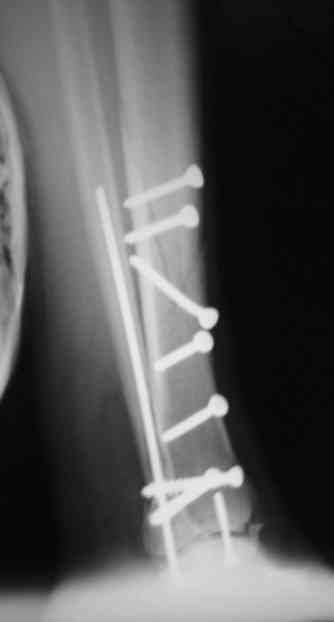

Re: Сложный внутрисуставной перелом голени

Рентгенограммы

А вид всей голени и стопы после операции?